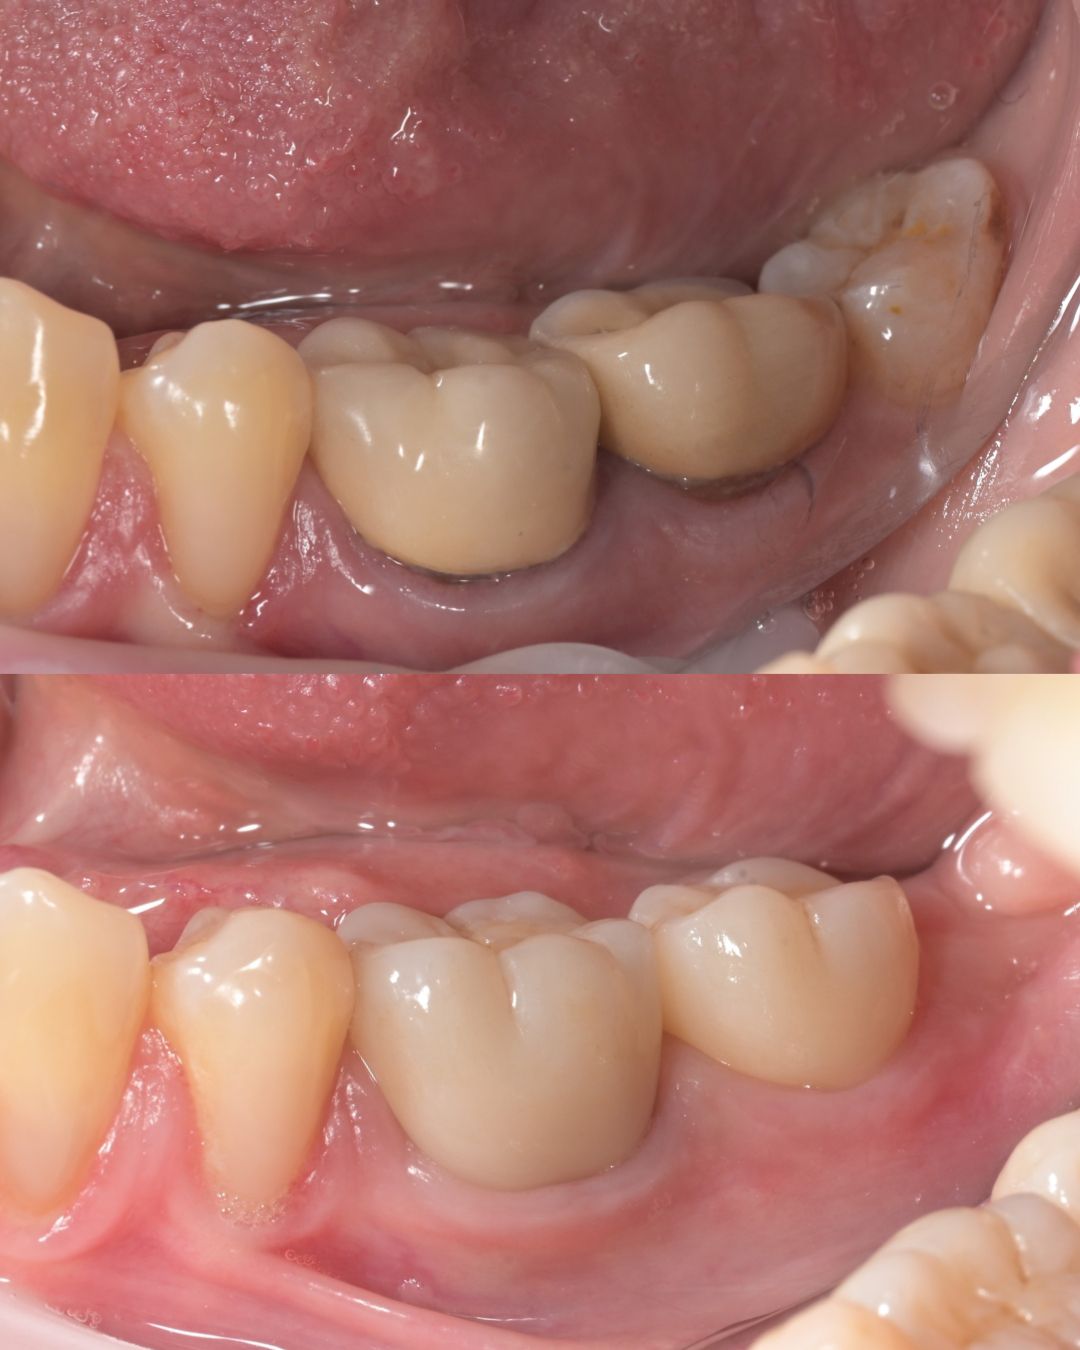

до и после